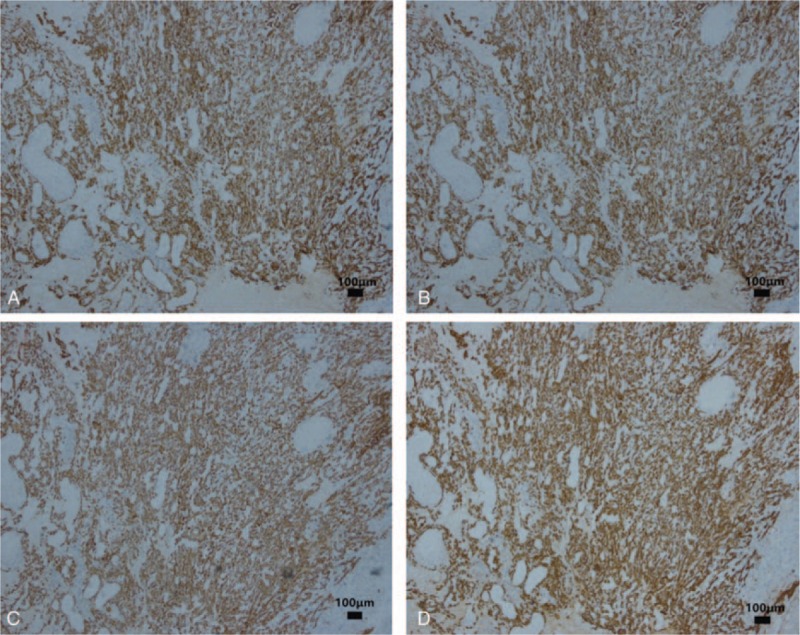

On immunohistochemistry, the sample was positive for several cytokeratins (CKs), including CK7 (Fig. 4A), CK19 (Fig. 4B), CK18, and pan-CK (AE1/AE3) (Fig. 4C). Immunohistochemistry also showed Vimentin and CEA staining (Fig. 4D). The sample was negative for smooth muscle actin, desmin, myoglobin, and S-100 protein.

Our case appears to be in agreement with the first theory. Owing to the expression pattern of CK and other markers, and the coexpression of CK and Vimentin, the sarcomatoid cells may be carcinoma cells with sarcomatoid differentiation or metaplastic carcinoma. As no heterologous sarcomatous elements were found, we used the term of “sarcomatoid carcinoma” instead of “carcinosarcoma.”